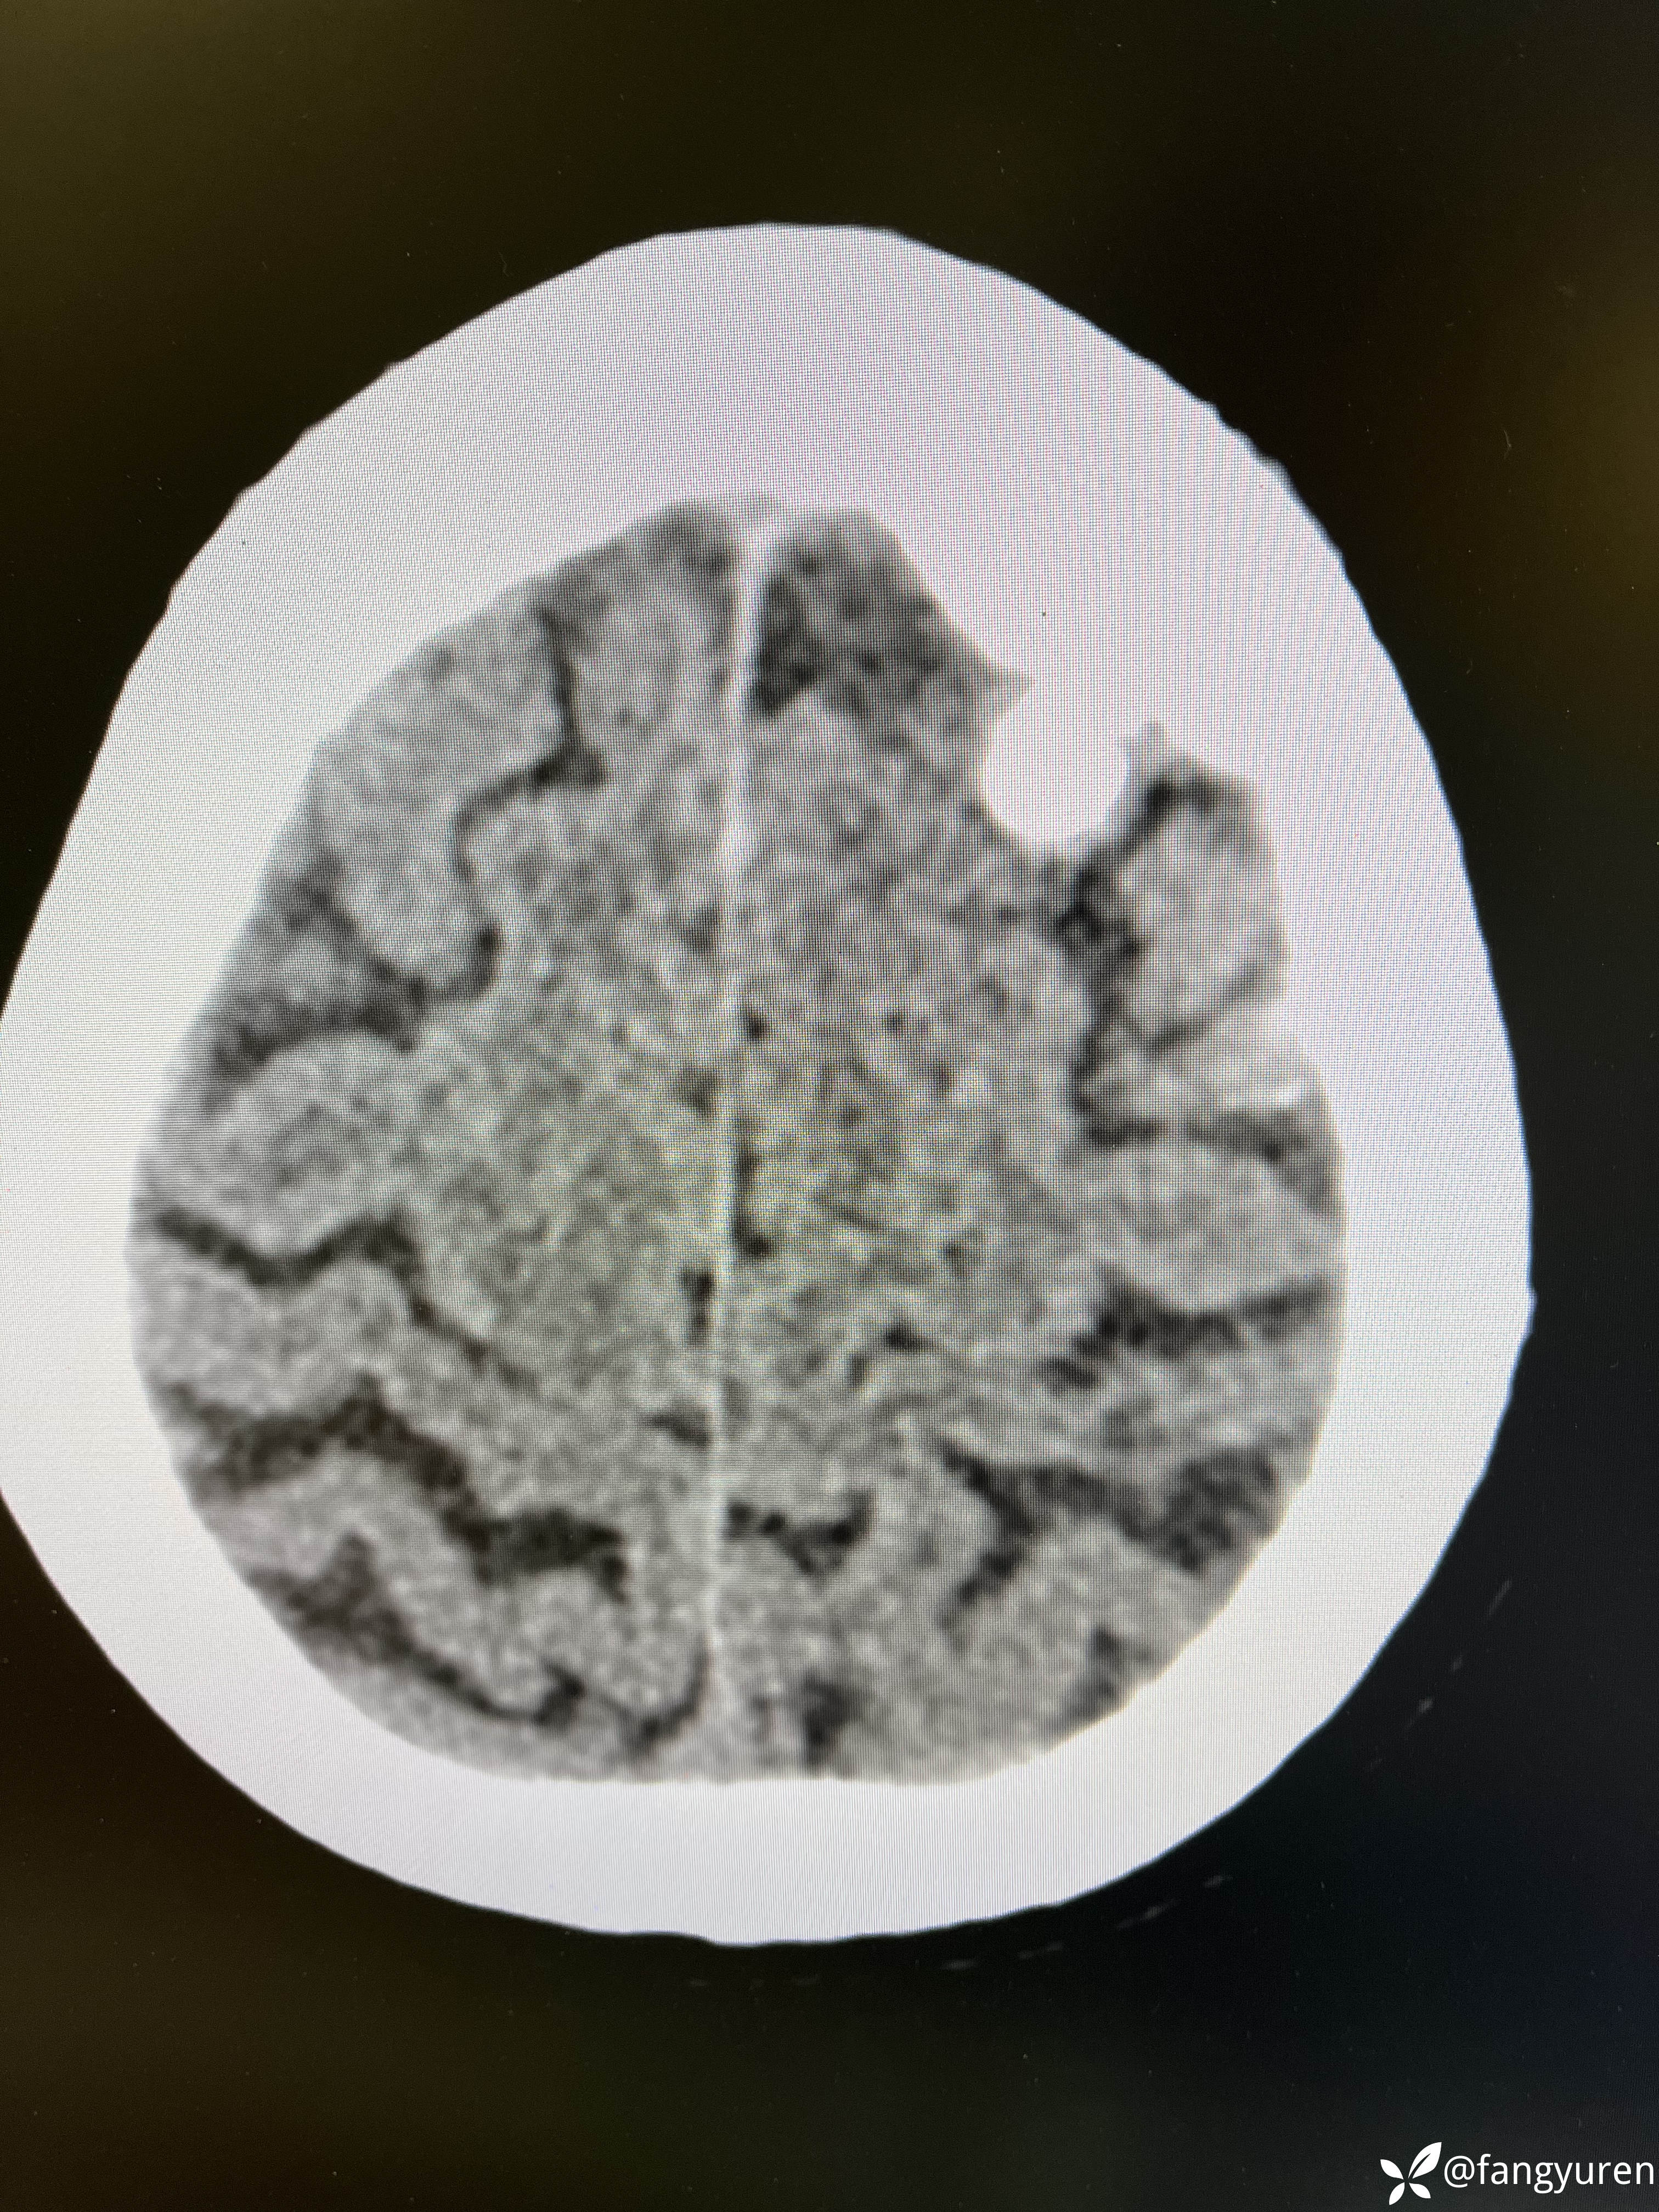

女66,头晕来摄影,发现大脑左侧纵裂旁、左侧额部颅骨下和右侧侧脑室后角见多发类圆形稍高、等、低密度影,部门钙化提示脑膜瘤。如图,蓝圈圈(详细请看视频)所示右侧侧脑室后角见类圆形低密度,周边钙化,考虑是什么,囊状脑膜瘤?多谢老师